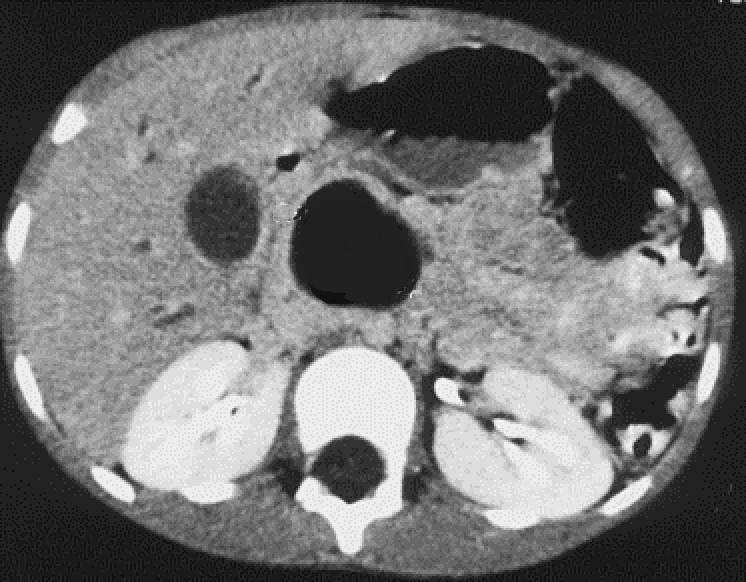

Tumeur

pancreblastome du queue du pancreas avec aspect

lesionnel tumoral hypodensite tres volumineuse ,lobulaire

en capsulaire ( fleche ) . Image radiologique

TDM coupe axiale a travers L2 |